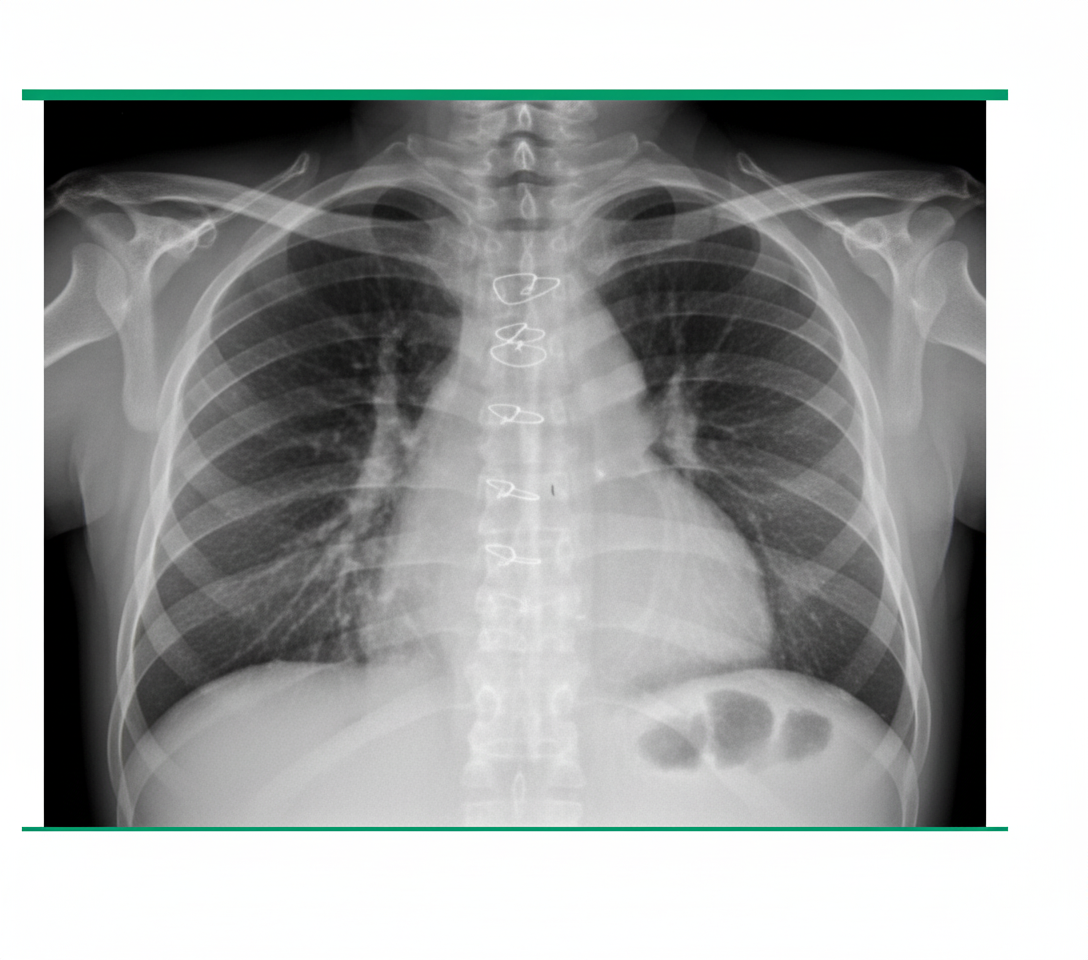

A 65-year-old man developed severe, acute onset breathlessness within a few hours of aortic valve replacement. What is the likely diagnosis based on a chest X-ray?

Explanation: ***Pericardial tamponade*** - **Acute breathlessness** following **cardiac surgery** strongly suggests pericardial tamponade due to **pericardial bleeding** or fluid accumulation. - Chest X-ray shows the classic **"water-bottle heart"** sign with **clear lung fields**, as the issue is cardiac compression rather than pulmonary pathology. *Gross bilateral pleural effusion* - Would show **bilateral blunting** of **costophrenic angles** and **opacification** of lower lung fields on chest X-ray. - Typically develops **gradually** over days rather than causing **acute severe breathlessness** within hours. *Left tension pneumothorax* - Chest X-ray would show **complete absence** of lung markings on the left side with **mediastinal shift** to the right. - Associated with **tracheal deviation** and **hyperexpanded** left hemithorax, not the water-bottle heart appearance. *Entire left lung collapse* - Would present with **complete opacification** of the left hemithorax and **mediastinal shift** toward the affected side. - Typically associated with **bronchial obstruction** rather than post-surgical cardiac complications.